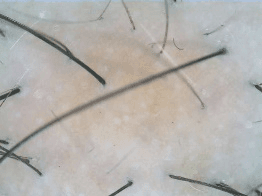

| Clear | ![]() | ![]() | ![]() | ![]() |

| Almost Clear | ![]() | ![]() | ![]() | ![]() |

| Moderate | ![]() | ![]() | ![]() | ![]() |

| Poor | ![]() | ![]() | ![]() | ![]() |

| Severe | ![]() | ![]() | ![]() | ![]() |